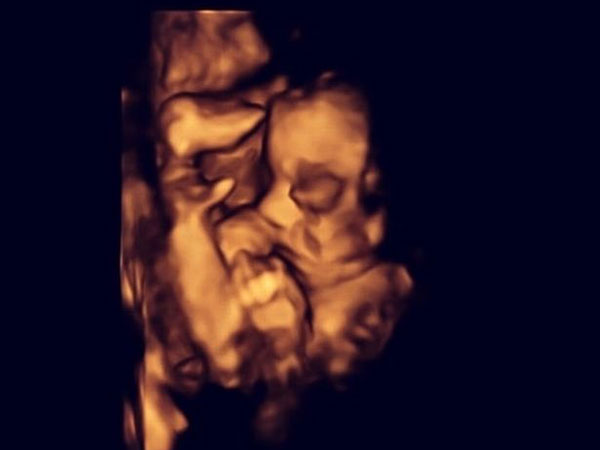

ಮಗುವನ್ನು ಗರ್ಭದಿಂದ ಹೊರತೆಗೆದು ಶಸ್ತ್ರಚಿಕಿತ್ಸೆ ನಡೆಸಿದರು!

ಆಧುನಿಕ ವೈದ್ಯ ವಿಜ್ಞಾನವು ಇಂದಿನ ದಿನಗಳಲ್ಲಿ ಯಾವ ರೀತಿಯಾಗಿ ಮುಂದುವರಿದಿದೆ ಎಂದರೆ, ದೇಹದ ಯಾವ ಭಾಗವು ನಿಷ್ಕ್ರೀಯವಾದರೂ ಅದನ್ನು ಸರಿಪಡಿಸುವಷ್ಟು. ಅದೇ ರೀತಿ ಎಲ್ಲೋ ಒಬ್ಬರಿಗೆ ಬೇಕಾಗಿರುವ ಹೃದಯವನ್ನು ಇನ್ನೆಲ್ಲಿಂದಲೋ ತಂದು ಜೋಡಣೆ ಮಾಡಿ ಪ್ರಾಣ ಕಾಪಾಡುವರು. ಅದೇ ರೀತಿಯಾಗಿ ಈಗ ಗರ್ಭದಲ್ಲಿರುವಂತಹ ಮಗುವಿಗೆ ಶಸ್ತ್ರಚಿಕಿತ್ಸೆ ನಡೆಸುವಷ್ಟು ವೈದ್ಯಕೀಯ ವಿಜ್ಞಾನವು ಮುಂದುವರಿದಿದೆ.

ಈ ಲೇಖನದಲ್ಲಿ ನಾವು ನಿಮಗೆ ಅಂತಹ ಒಂದು ವೈದ್ಯಕೀಯ ವಿಜ್ಞಾನದ ಸಾಧನೆ ಬಗ್ಗೆ ಹೇಳಲಿದ್ದೇವೆ. ಗರ್ಭದಲ್ಲಿರುವ ಮಗುವಿಗೆ ಶಸ್ತ್ರಚಿಕಿತ್ಸೆ ಮಾಡಲು ವೈದ್ಯರು ಯಶಸ್ವಿಯಾಗಿದ್ದಾರೆ. ಈ ಘಟನೆ ಬಗ್ಗೆ ಓದಿದರೆ ಆಗ ನಿಮಗೆ ವೈದ್ಯಕೀಯ ವಿಜ್ಞಾನವು ಇಷ್ಟು ಮುಂದುವರಿದೆಯಾ ಎಂದು ನಿಬ್ಬೆರಗಾಗಬಹುದು.

26ರ ಹರೆಯದ ಮಹಿಳೆ ಮತ್ತು ಆಕೆಯ ಸಂಗಾತಿಗೆ ಗರ್ಭಪಾತ ಮಾಡಿಸಿಕೊಳ್ಳಲು ವೈದ್ಯರು ಸಲಹೆ ನೀಡಿದರು. ಯಾಕೆಂದರೆ ಗರ್ಭದಲ್ಲಿ ಇರುವಂತಹ ಮಗುವಿಗೆ ಸ್ಪಿನಾ ಬೈಫಿಡಾ ಎನ್ನುವ ಸಮಸ್ಯೆ ಇತ್ತು. ಗರ್ಭಧಾರಣೆಯ 20ನೇ ವಾರದ ನಿಯಮಿತ ಸ್ಕ್ಯಾನಿಂಗ್ ವೇಳೆ ವೈದ್ಯರಿಗೆ ಈ ಸಮಸ್ಯೆ ಬಗ್ಗೆ ತಿಳಿದುಬಂತು. ಗರ್ಭದಲ್ಲಿರುವಂತಹ ಮಗುವಿನ ತಲೆಯು ಸರಿಯಾದ ಗಾತ್ರದಲ್ಲಿ ಇಲ್ಲವೆಂದು ವೈದ್ಯರಿಗೆ ಈ ವೇಳೆ ತಿಳಿದು ಬಂತು.

ಗರ್ಭದಲ್ಲಿರುವಂತಹ ಮಗುವಿನ ಬೆನ್ನುಮೂಳೆಯು ಸರಿಯಾಗಿ ಬೆಳವಣಿಗೆ ಆಗದೆ ಇರುವಂತಹ ಪರಿಸ್ಥಿತಿಯನ್ನು ಸ್ಪಿನಾ ಬೈಫಿಡಾ ಎಂದು ಹೇಳುವರು. ಇದರ ಪರಿಣಾಮವಾಗಿ ಮುಂದೆ ಮಗು ಜನಿಸಿದ ಬಳಿಕ ಅದಕ್ಕೆ ಸರಿಯಾಗಿ ನಡೆದಾಡಲು ಆಗದು.

ವೈದ್ಯರು ಆ ದಂಪತಿಗೆ ಹೊಸ ಆಯ್ಕೆ ನೀಡಿದರು. ಇದರಲ್ಲಿ ಗರ್ಭದಲ್ಲಿಯೇ ಮಗುವಿನ ಪರಿಸ್ಥಿತಿಯನ್ನು ಜನಿಸುವ ಮೊದಲೇ ಶಸ್ತ್ರಚಿಕಿತ್ಸೆ ಮೂಲಕವಾಗಿ ಸರಿ ಮಾಡುವುದು. ಈ ಶಸ್ತ್ರಚಿಕಿತ್ಸೆಯಲ್ಲಿ ತಾಯಿ ಗರ್ಭದಿಂದ ಮಗುವನ್ನು ಹೊರಗೆ ತೆಗೆದು, ಬಳಿಕ ಮಗುವಿನ ಬೆನ್ನುಮೂಳೆಯನ್ನು ಸರಿಪಡಿಸುವುದು. ಇದರಿಂದ ಮುಂದೆ ಮಗು ಜನಿಸಿದ ಬಳಿಕ ಅದಕ್ಕೆ ಸಾಮಾನ್ಯ ಜೀವನ ಸಾಗಿಸಲು ಸಾಧ್ಯವಾಗುವುದು.

ಮಗುವನ್ನು ಮತ್ತೆ ಗರ್ಭದೊಳಗೆ ಇಡಲಾಯಿತು

ಶಸ್ತ್ರಚಿಕಿತ್ಸೆ ಬಳಿಕ ಮಗುವನ್ನು ಮತ್ತೆ ಅದೇ ಸ್ಥಿತಿಯಲ್ಲಿ ಗರ್ಭದಲ್ಲಿ ಇಡಲಾಯಿತು. ಇದರಿಂದ ಮಹಿಳೆಯು ಸಂಪೂರ್ಣ ಗರ್ಭಧಾರಣೆ ಸಮಯವನ್ನು ಪೂರೈಸಿ, ಮಗುವಿಗೆ ಜನ್ಮ ನೀಡಬೇಕು. ಈ ಶಸ್ತ್ರಚಿಕಿತ್ಸೆಯು ತುಂಬಾ ಯಶಸ್ವಿಯಾಗಿದೆ ಮತ್ತು ಇದನ್ನು ಪೋಷಕರು ಆಯ್ಕೆ ಮಾಡಿಕೊಳ್ಳಬಹುದು ಎಂದು ವೈದ್ಯರು ಹೇಳಿದ್ದಾರೆ. ಶೇ. 80ರಷ್ಟು ದಂಪತಿಯು ಇಂತಹ ಸಮಸ್ಯೆಯಿದ್ದಾಗ ಗರ್ಭಪಾತ ಮಾಡಿಸಿಕೊಳ್ಳುವರು ಎಂದು ಅಧ್ಯಯನ ವರದಿಗಳು ಬಹಿರಂಗಪಡಿಸಿವೆ. ಇದೊಂದು ವೈದ್ಯಕೀಯ ಲೋಕದ ಅದ್ಭುತವಾದ ಶಸ್ತ್ರಚಿಕಿತ್ಸೆ ಎಂದರೆ ತಪ್ಪಾಗದು. ಇಂತಹ ವೈದ್ಯಕೀಯ ವಿಜ್ಞಾನದಿಂದಾಗಿ ಮಕ್ಕಳು ವಿಕಲಾಂಗರಾಗಿ ಹುಟ್ಟುವಂತಹ ಸಮಸ್ಯೆಯು ಕಡಿಮೆಯಾಗಬಹುದು. ಈ ಶಸ್ತ್ರಚಿಕಿತ್ಸೆ ಬಗ್ಗೆ ನಿಮ್ಮ ಅಭಿಪ್ರಾಯ ಏನು? ನಿಮ್ಮ ಅನಿಸಿಕೆಗಳನ್ನು ಕಮೆಂಟ್ ಬಾಕ್ಸ್ ನಲ್ಲಿ ನಮಗೆ ಬರೆದು ತಿಳಿಸಿ.